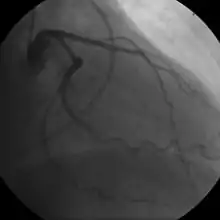

- Coronary angiography

In "stable" angina, chest pain with typical features occurring at predictable levels of exertion, various forms of cardiac stress tests may be used to induce both symptoms and detect changes by way of electrocardiography (using an ECG), echocardiography (using ultrasound of the heart) or scintigraphy (using uptake of radionuclide by the heart muscle). If part of the heart seems to receive an insufficient blood supply, coronary angiography may be used to identify stenosis of the coronary arteries and suitability for angioplasty or bypass surgery.[64]